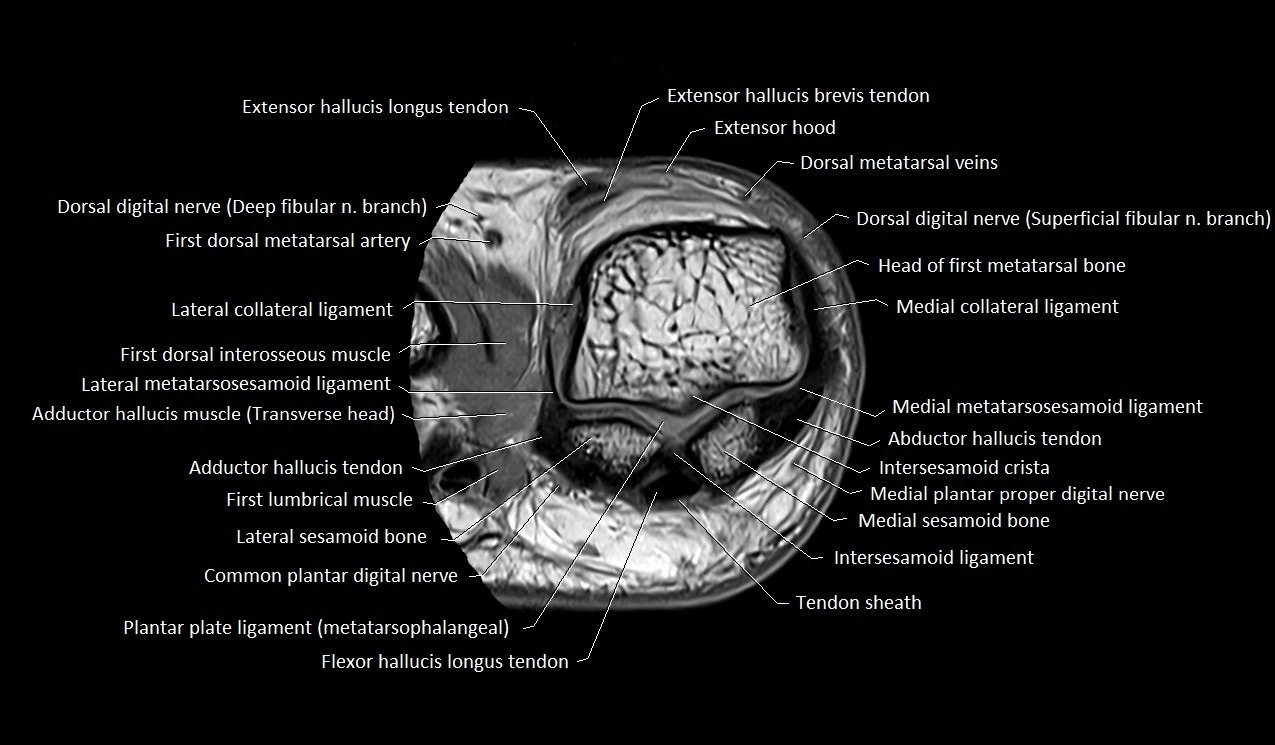

MRI image

image